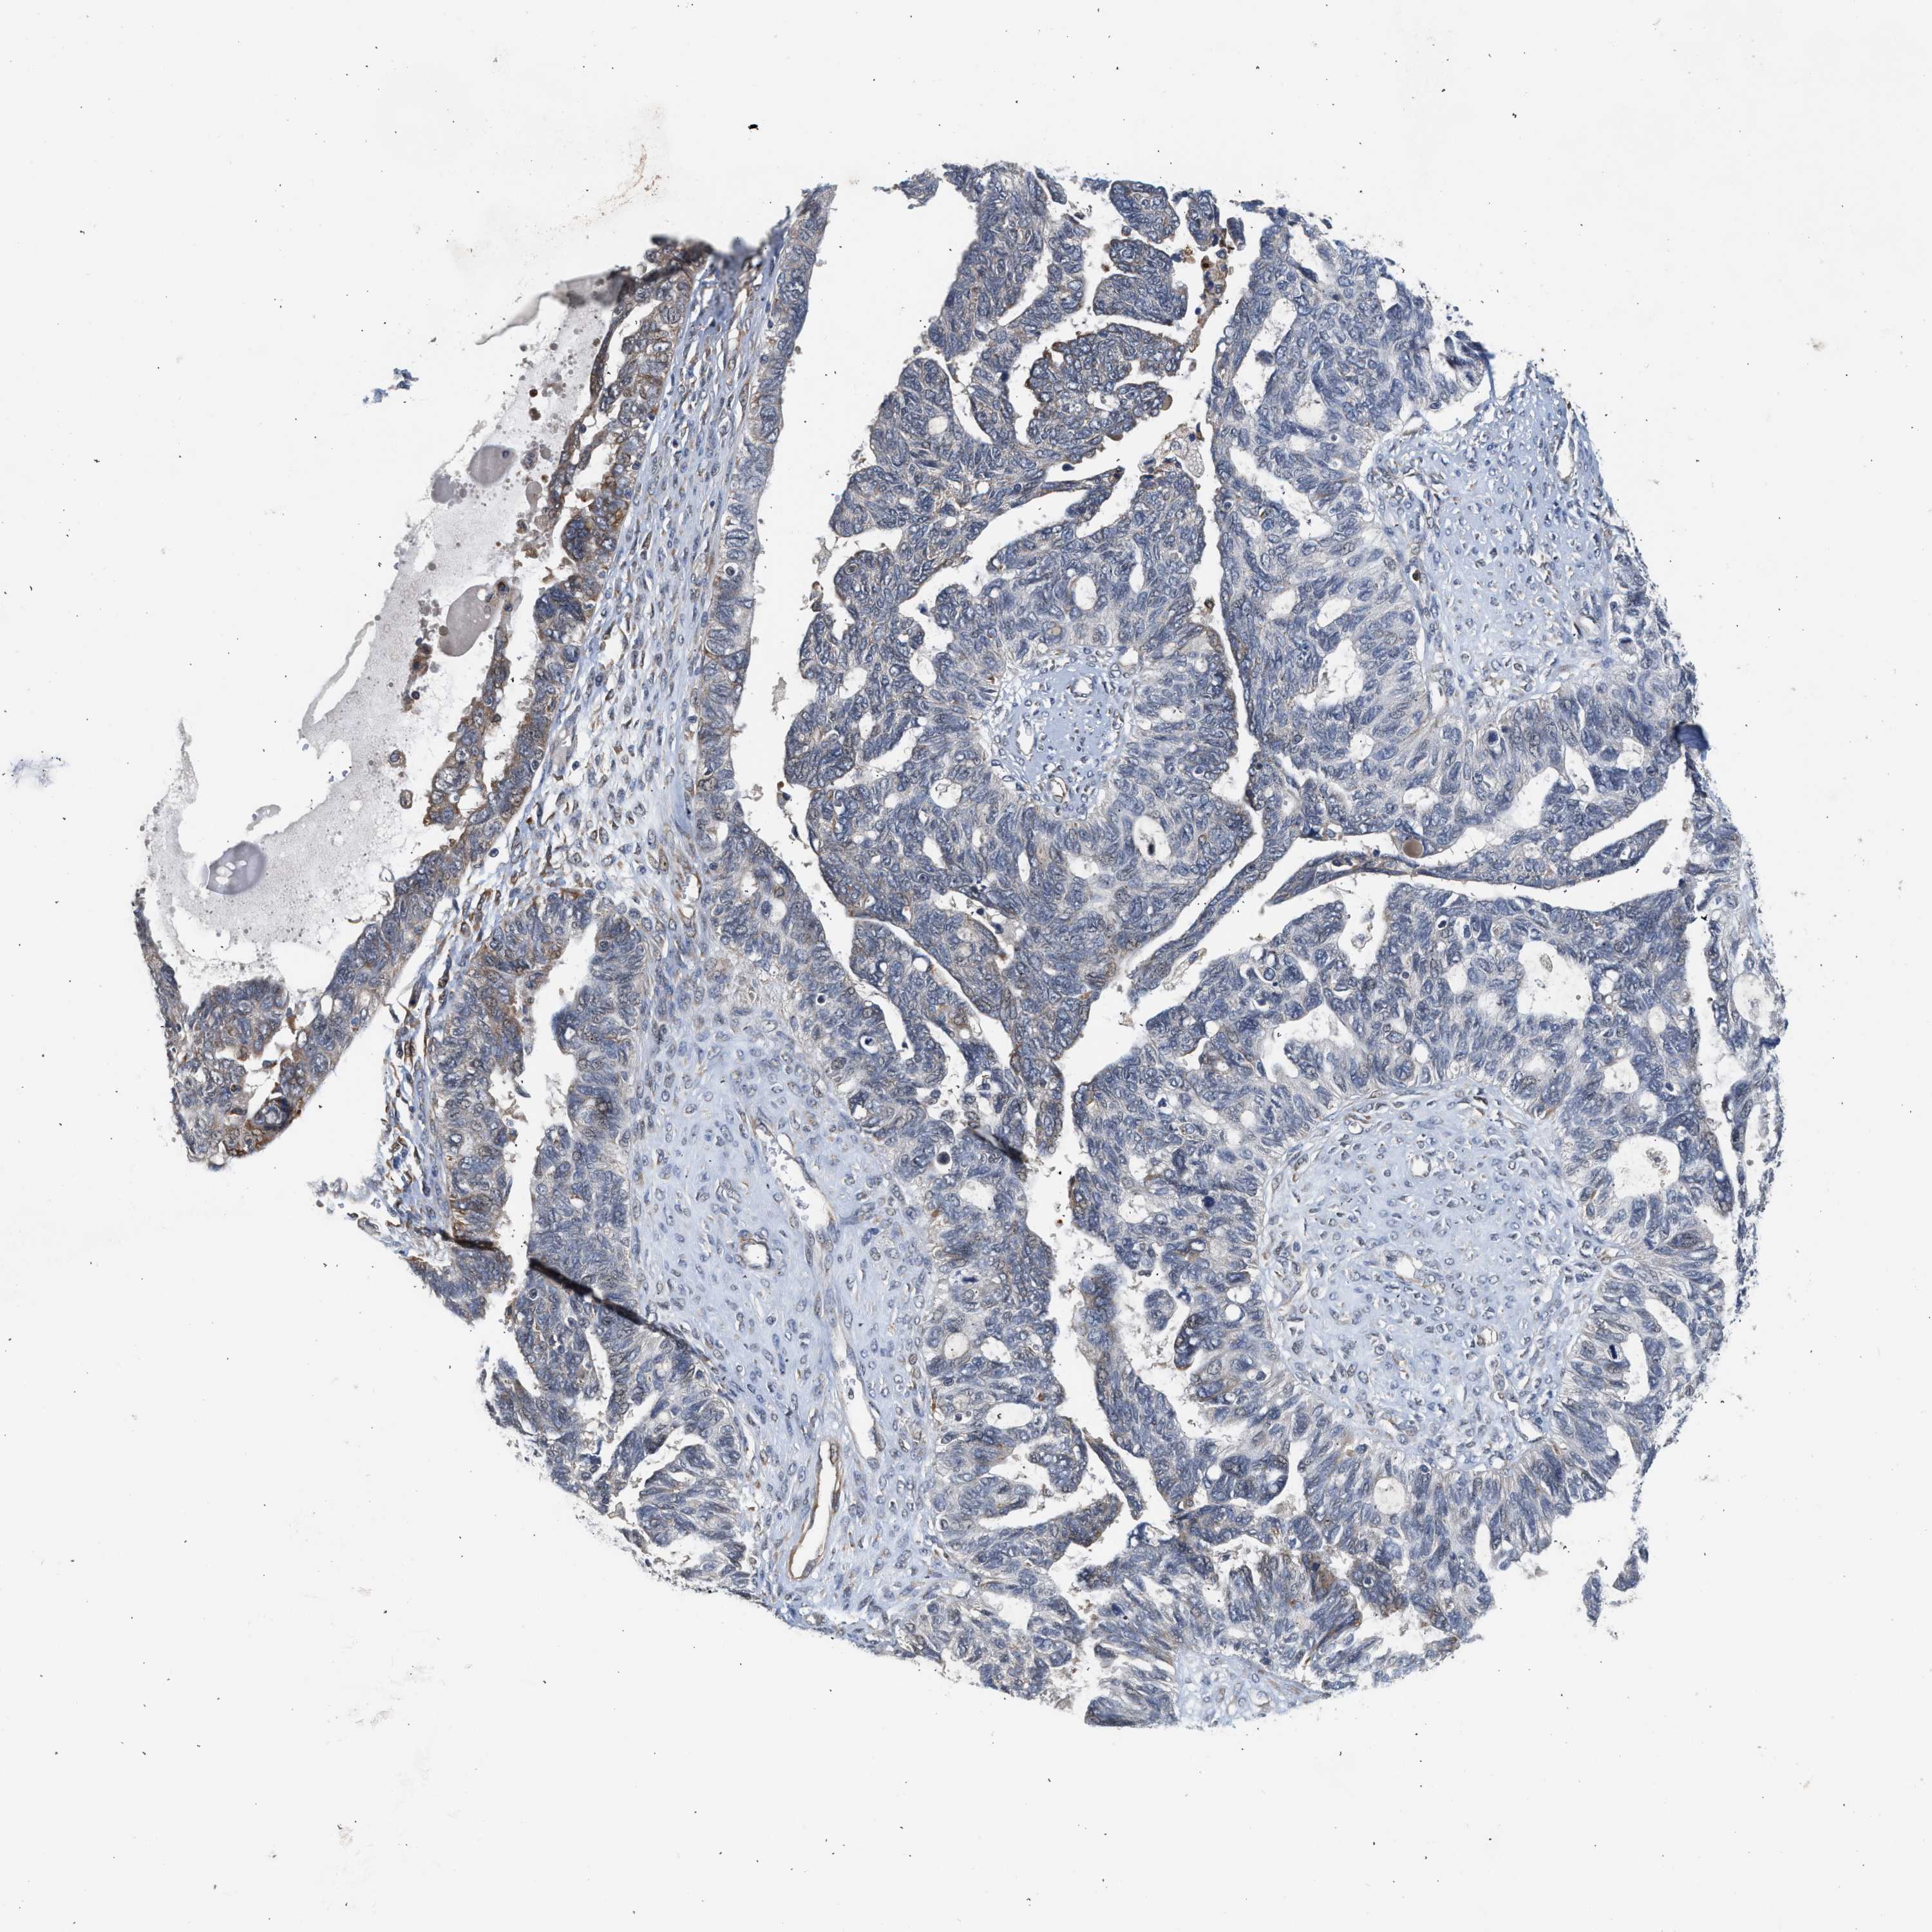

OVARIAN CANCER - Protein expressioni

A mouse-over function shows sample information and annotation data. Click on an image to view it in a full screen mode. Samples can be filtered based on level of antibody staining by selecting one or several of the following categories: high, medium, low and not detected. The assay and annotation is described here.

Note that samples used for immunohistochemistry by the Human Protein Atlas do not correspond to samples in the TCGA dataset.

Antibody stainingi

Antibody staining in the annotated cell types in the current human tissue is reported as not detected, low, medium, or high, based on conventional immunohistochemistry profiling in selected tissues. This score is based on the combination of the staining intensity and fraction of stained cells.

Each image is clickable and will lead to virtual microscopy that enables deeper exploration of all samples and also displays staining intensity scores, fraction scores and subcellular localization as well as patient and tissue information for each sample.

Antibody HPA023202

Antibody CAB017030

Cystadenocarcinoma, serous, NOS

Carcinoma, endometroid

Cystadenocarcinoma, mucinous, NOS

Carcinoma, NOS